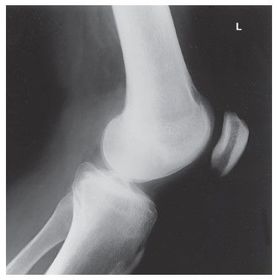

Lateral Knee Mediolateral 40 SID 10x12 IR in table BUCKY - pt lateral recumbent w/ knee flexed 20-30 degrees so patella is perpendicular to IR - CR angled 5-7 degrees cephalic @ 1 in distal to medial epicondyle (Always angle for lateral) *seeing the adductor tubercle indicates the pt is underrotated* *seeing the distal borders of femoral condyles NOT superimposed indicates an incorrect cephalic CR angle*